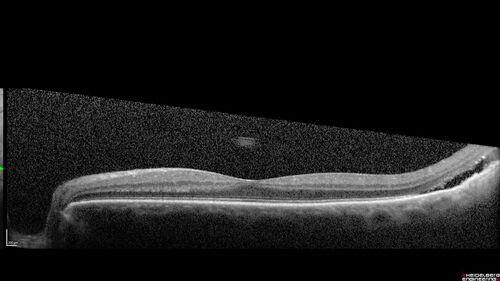

Class 2 choroidal melanoma

48 year old man with no visual complaints referred by optometrist.

Brachytherapy was done and biopsy showed a class 2 melanoma. 2 years later the patient developed liver metastases.